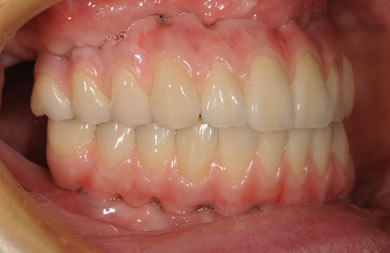

骨再生スピードインプラント治療+AGC連結セラミック治療

| 治療方針 | 骨再生療法にて骨量を回復するとともに軟組織も移植し、機能的回復だけでなく審美的回復も行う。 | ||||||||||||||||||||||||||||||||

| 治療内容 | インプラント12本(サイナスリフト+GBR+抜歯即日スピードインプラント+遊離歯肉移植)、AGCハイブリッドセラミック連結ブリッジ2装置(上顎・下顎)、テンポラリーインプラント2本 | ||||||||||||||||||||||||||||||||

| 総治療費 | 6,019,650円 | ||||||||||||||||||||||||||||||||

| 治療期間 | 1年0ヶ月 |